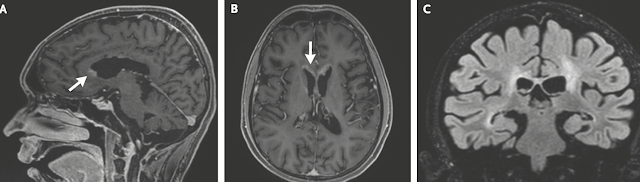

頭部の磁気共鳴画像(MRI)では、脳室周囲の白質に広い範囲で信号異常が見られ、

脳室に結節や軟膜の造影効果が認められた

視神経路に沿って対称的な信号異常が見られた

MRIではやたら脳室周囲の異常陰影が目立ちますね

脳室周囲炎といえば、アクアポリン4に関わるNMOをまずは考えたくなります

本症例のMRIはこんな感じでした

・脳室上衣に沿って、脳室壁に広範囲に浸潤する特徴がある(脳室上衣下浸潤)

脳室壁に結節状の多発病変として抽出される